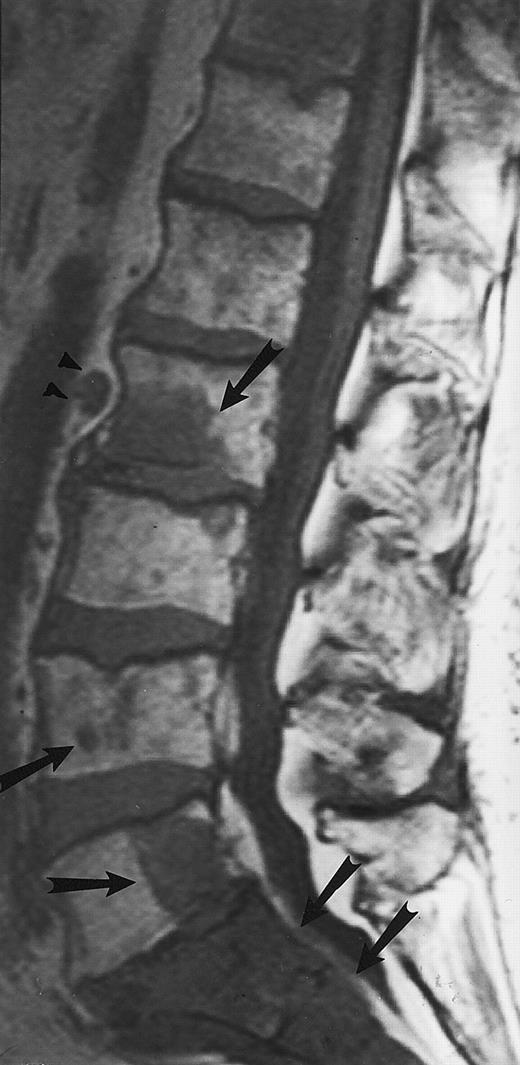

Lymphoma: multifocal bone marrow involvement. Sagittal T1-weighted (500/10, TR/TE) MR image of the lumbar spine shows multiple foci of bone marrow replacement (arrows). This appearance of lymphomatous involvement of the bone marrow is similar to bone metastases. Note extraosseous mass in the presacral space with apparent preservation of the bony cortex and small retroperitoneal lymph node at the level of L2 (arrowheads).

Its superior contrast resolution compared with CT makes MR imaging the modality of choice for the demonstration of soft tissue involvement. We have observed that extraosseous tumor in patients with lymphoma often occurs without obvious destruction of the cortical bone, reflecting the permeative nature of the tumor. MR images may show extensive involvement of the marrow and extraosseous soft tissues, with tumor “wrapped” around an apparently intact bony cortex48 (Figs 11 and 12). On bone radiographs and on CT, the involved bones may appear normal. This characteristic appearance of the extraosseous extent of lymphomatous involvement of the bone marrow is not pathognomonic for this disease and may be observed in other malignancies, particularly those of small cell origin. However, its presence may raise the possibility of lymphoma and direct the appropriate work-up. Caution should be taken to avoid misdiagnosing retroperitoneal lymphadenopathy for bone marrow involvement with extraosseous extension of tumor. Recently, Fenstermacher et al49 reported a 100% accuracy in the diagnosis of primary lymphoma of the bone versus osteosarcoma and Ewing sarcoma when no cortical destruction was detected in the area of bone marrow involvement and soft-tissue mass.